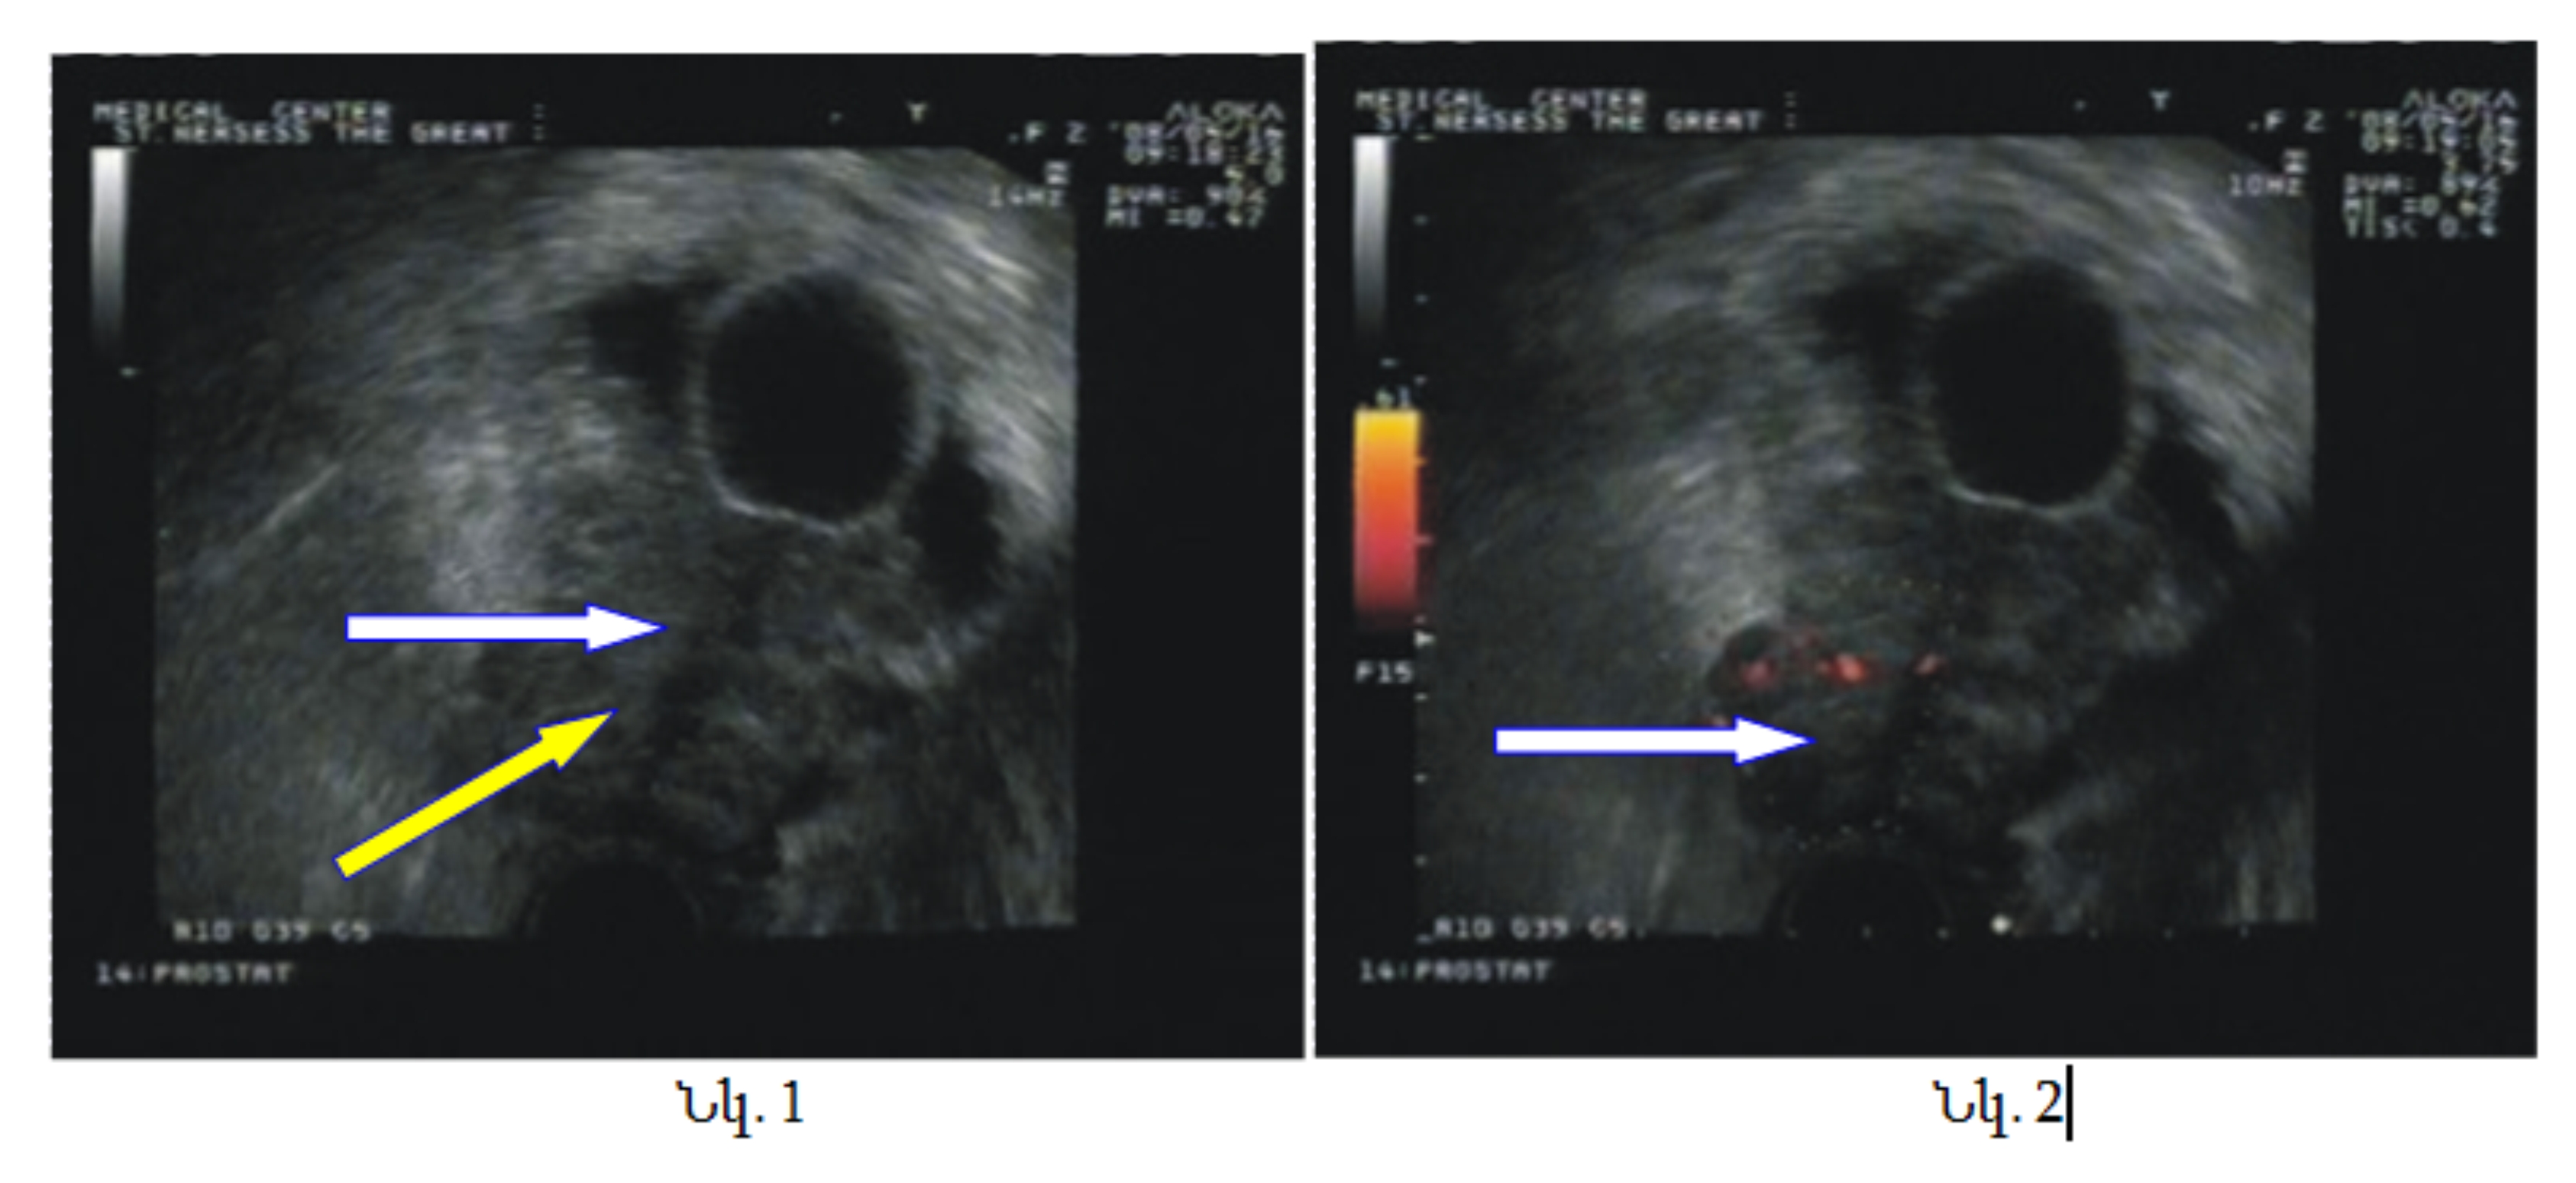

Վերջում ցանկանում ենք ներկայացնել մեր կատարած հետազոտություններից մեկ դեպք, երբ գորշ սանդղակով շագանակագեղձի տրանսռեկտալ ուլտրաձայնային հետազոտության ժամանակ աջ բլթում հայտնաբերվել է հիպոէխոգեն գոյացություն (նկ. 1, դեղին սլաք), որի բիոպսիայից հյուսվածքային կտոր չի ստացվել (հավանաբար կիստոզ գոյացություն է): Սակայն հարակից զոնայից, որը էներգետիկ (նկ. 2) և գունավոր (նկ. 3) ռեժիմներով հիպերվասկուլյար օջախ է, իսկ գորշ սանդղակով` իզոէխոգեն-ստացվել է շագանակագեղձի ադենոկարցինոմա Գլիսոն 3+3=6 բալ: